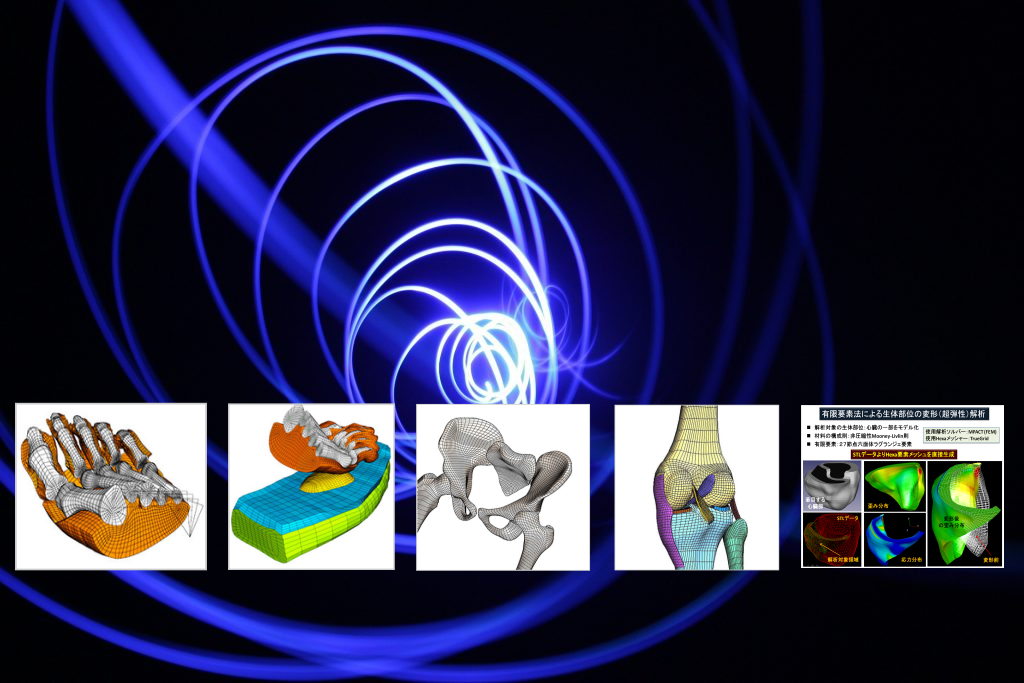

- 2011/2/7 医療用解析ソフトSPH Medical Solutionを更新しました。

講演題目:SPH粒子法によるバイオメカニックス分野への応用 - 2011/1/20 米国South Carolina大学LAMSSと超音波による新しい安全性